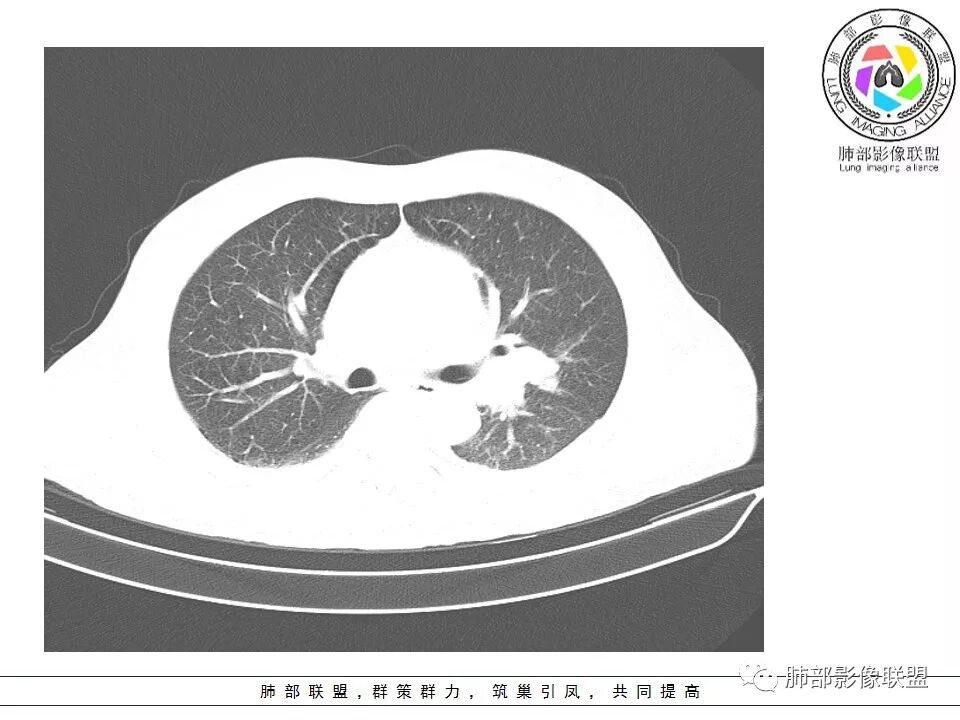

老年男性咳嗽,左下近肺门团块影,不规则强化伴坏死,左下肺静脉、支气管旁淋巴结转移受压、并侵犯左下支气管,考虑鳞癌,鉴别小细胞。

男,70岁,左下肺肿块影,分叶,增强有较大范围坏死,左肺门肿块影,跨叶,包绕支气管与肺门血管,致其狭窄考虑为淋巴结肿大,综合考虑为恶性肿块,鳞癌并左肺门淋巴结转移

肺门淋巴结有肿大,支气管内有肿物,这么大病灶没有坏死,我考虑神经内分泌癌或者小细胞肺癌。鳞癌不符合没看到明显阻塞

老年男性,咳嗽主诉,胸部ct左侧肺门新生物,支气管阻塞,不均匀强化,伴淋巴结肿大,考虑鳞癌,鉴别小细胞肺癌。

恶性肿瘤没有问题,这一层如果是指状突起我考虑小细胞癌

老年男性,左下占位,类圆丶浅分叶,无毛刺及胸膜凹陷征,各支气管狭窄,增强不均匀强化,左肺门淋巴结肿大考虑恶性,小>鳞

患者老年男性,以咳嗽就诊,胸CT:左肺下叶占位,病灶呈膨胀性生长,左肺下叶气管明显狭窄,病灶边缘光滑,并可见分叶,增强可见病灶内低密度区,病灶边缘强化。考虑恶性,鳞?肉瘤?

左下肺团块影,不规则强化伴坏死,左下肺静脉、支气管旁淋巴结转移,并侵犯左下支气管,考虑恶性病变,小细胞?

左肺主支气管下肿块,病变包绕并向腔内生长,无阻塞性肺炎,内部可见穿行血管,增强后可见实性明显强化,纵隔淋巴结肿大,老年男性,考虑:神经内分泌癌(类癌、小细胞癌),淋巴瘤,鳞癌

病史:男,70岁,咳嗽;影像:肺门淋巴结,淋巴结内血管毛糙不规则,静脉期,转移大,左心房左下静脉下支是否有累及。主体病灶,呈扇形,沼泽样,指状突起。肺气肿并不明显,左侧少许,左上叶支气管狭窄,肺窗点状凸起,纵膈窗并没有,考虑淋巴结压迫所致。老王曾经说过,小细胞来不及跑得快,胸膜目前没有积液是否是这个原因?诊断:恶性,小细胞肺癌;鉴别:鳞癌,不太像,其他神经类分泌恶性肿瘤;处置:经皮穿刺或EBUS。

左下肺占位性病变,伴肺门淋巴结肿大,强化示不均匀明显强化,可见边界不清坏死区,考虑恶性肿瘤!病灶缺乏分叶及毛刺,整体圆顿,病理倾向大细胞!

左下肺肿块,不均匀强化,其内可见坏死或粘液,更多考虑坏死,左下肺支气管堵塞,左肺门多发肿大淋巴结,左下肺癌,鳞癌可能性大鉴别于小细胞癌

病灶从外向里长,气管狭窄,血管受侵犯,肺门纵膈淋巴结肿大,考虑恶性,首先考虑小细胞癌

左下肺占位伴肺门淋巴结肿大,病灶呈膨胀性生长,左肺下叶气管明显狭窄推移,病灶边缘光滑,并可见分叶,增强可见坏死,病灶边缘强化,阻塞性肺炎不明显,恶性没问题,考虑低分化腺癌,鉴别神经内分泌肿瘤,无冰冻感觉,坏死明显,小细胞不支持,排除大细胞与类癌

老年男性,症状轻。左肺下叶类圆形肿块,边界清楚,分叶不明显,其内无空泡征,边缘无毛刺及胸膜牵拉,远端无阻塞性肺炎。左肺门影增大。增强扫描左肺下叶肿块可疑轻度强化(无平扫对比),局部见小尾巴征。左肺门区见不规则形团块,似多个结节融合,肺动脉受压穿行于病灶中,形成冰冻肺门感觉,局部层面似见肺门区团块与左肺下叶肿块相连。综合考虑小细胞肺癌(SCLC)。

左肺下叶肿块,边缘膨隆,分叶略浅,占位效应明显,远端没有明显花花草草,其内部不均匀强化,坏死边界不清,可见受累的强化血管穿行,是否有钙化?没有平扫,不清楚;同侧肺门淋巴结受累,包绕支气管生长,并突入下叶支气管,导致管腔闭塞及狭窄,考虑恶性没问题,肿瘤既有由外向内生长侵犯又有冰山征的感觉,小>类癌>低分化腺>鳞

病灶从外向内生长,气管狭窄,血管受侵犯,肺门纵膈淋巴结肿大,考虑恶性,腺癌。鉴别小细胞肺癌。

左下肺占位,边缘分叶彭隆,远端无明显阻塞性炎性,考虑外朝内生长为主,增强扫描边缘及病灶内均可见强化,血管破坏。考虑恶性,间叶组织来源,肉瘤?

段支气管管壁破坏比较明显了,小细胞可以破坏力这么强吗?

左肺下叶肿块,内部坏死明显,整体从外向内生长,下叶支气管及舌叶支气管被包绕生长,肺门区淋巴结肿大,坏死。远端无明显阻塞及不张,综合来看,恶性肯定,肺癌,整个病灶有分别有支持小细胞、鳞癌,腺癌及肉瘤样癌的地方,但又不典型,以低分化腺癌或肉瘤样癌或混合性癌(腺癌小细胞混合,低化分腺鳞癌混合),神经内分泌癌可能性大,单纯的鳞癌或小细胞癌有可能,但确实不典型了。至于间叶来源的恶性肿瘤,很少这样从向外内生甚至包绕支气管壁生长,再加上相对罕见,可能性小。

这个坏死还是有吧,我觉得定不到小细胞啊…

只能说应该不是鳞癌,生长方式应该起源于周围胸膜下

坏死面积还是比较大的,没有明显阻塞性肺炎和肺不张

腔外浸润为主,腔内无明显堵塞,原发肿块推移支气管为主,边缘光滑,轻微分叶,肺门引流区淋巴结肿大,而纵隔淋巴结无明确受累,综合考虑,癌:低分化腺癌?大细胞癌?肉瘤样癌?间叶组织肿瘤:肺肉瘤,罕见

张继荣:

男,70岁,咳嗽,无其它症状及化验检查结果,无MPR图像

左肺门乱乱的,有血管受压表现,有支气管腔内占位表现,肺门淋巴结肿大肯定是有的;左肺下叶见一巨大包块,边缘光滑,内侧又一个切迹,考虑是病变受到了小叶间隔阻挡造成的其内部大部分不强化,但有局部一小片强化;壁不均匀环形强化,总体较薄;周围没有阻塞性肺炎,感染性病变应该是不考虑的,因为周围清楚,也没有感染的症状,还是考虑肿瘤性病变;关键是它边缘光滑,内部应该是坏死,但有强化提示坏死不彻底,这么大了,边缘恶性征象不明显,不符合腺癌,鳞癌呢也不太符合,阻塞性肺炎没有,坏死太明显了,这么大,边缘光滑,坏死明显,符合肉瘤和肉瘤样癌,不除外小细胞肺癌